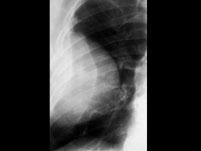

问题 下列描述符合周围型肺癌的X线表现为()

选项 A.肺野周围弥漫性圆形块影 B.块影边缘模糊毛糙 C.较大肿块中心部分坏死液化 D.大肿块内壁不平 E.多有明显液平面

答案 BD